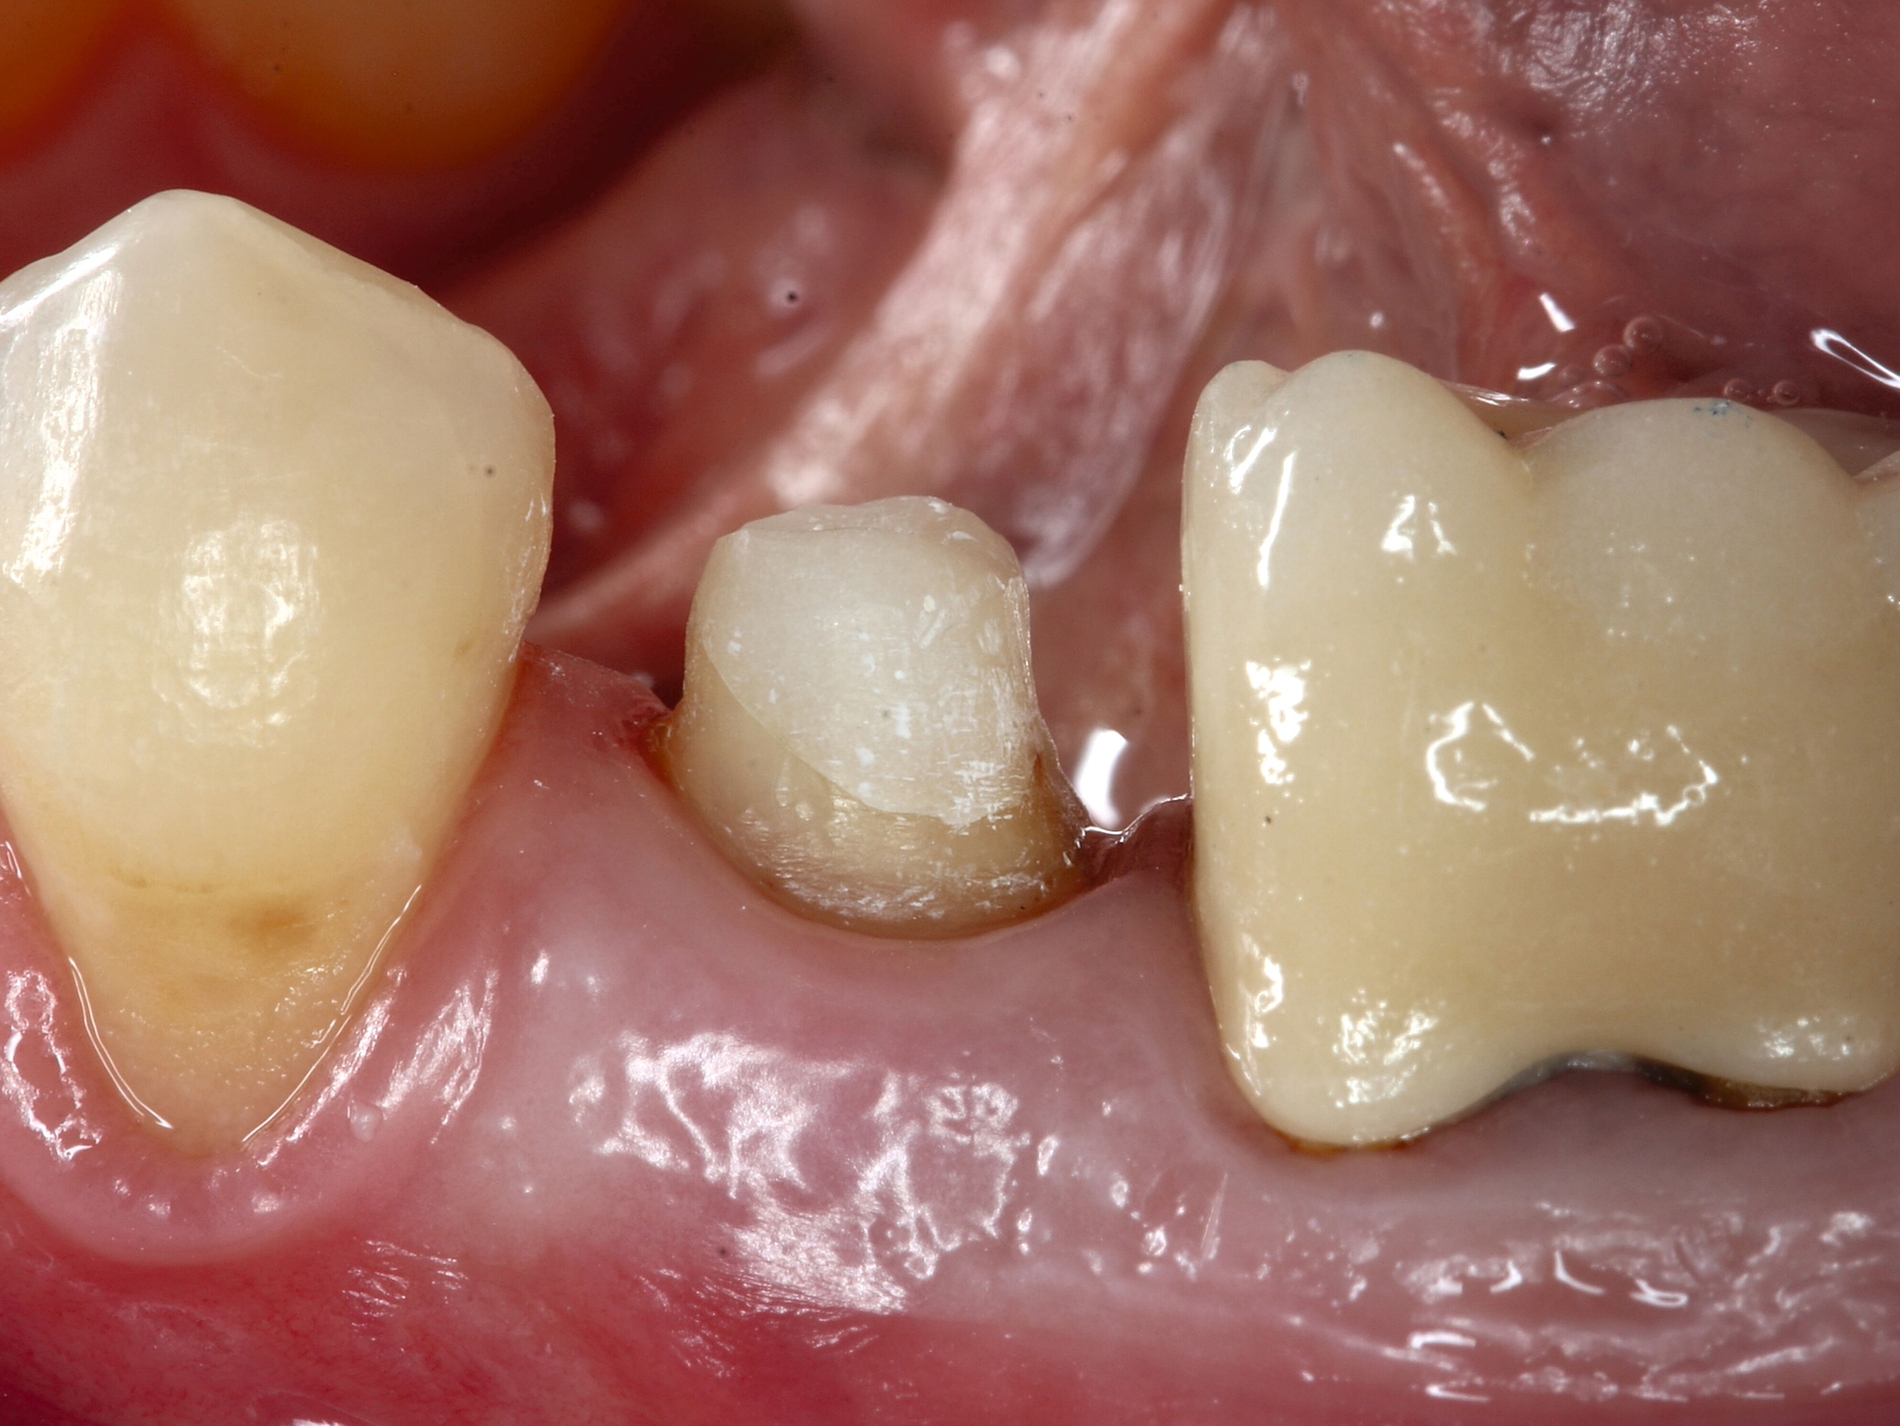

Schnelle kieferorthopädische Extrusionen im Sinne einer präprothetischen Maßnahme können zudem auch im Seitenzahnbereich indiziert sein, wenn für eine nachfolgende Kronenversorgung die notwendigen Voraussetzungen geschaffen werden sollen (ausreichende Stumpfhöhe, Einhaltung der biologischen Breite, Schaffung des Ferrule-Designs) [Gariulo et al., 1961; Juloski et al., 2012; Nugala et al., 2012] unter Einhalten eines Kronen-Wurzel-Verhältnisses von 1:1 [Grossmann und Sadan, 2005] (Abbildung 3).